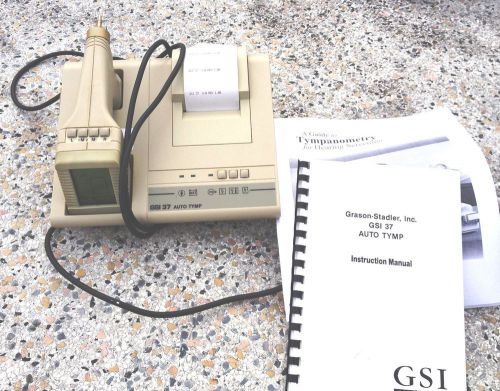

Tympanometry Grason-Stadler, Inc. GSI 37 Auto Temp